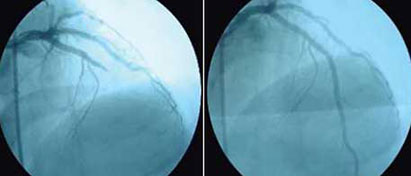

El 65% de los pacientes se estratificaron en un riego alto de acuerdo con la escala GRACE,8 con alta frecuencia de factores de riesgo, tales como: diabetes mellitus, hipertensión y tabaquismo. El 50% de los pacientes con IAM CEST no recibió una alternativa de reperfusión, que es la piedra angular del tratamiento, mientras que el 42% recibió terapia fibrinolítica (TF), y 8% recibió intervención coronaria percutánea (ICP) en una sala de Hemodinamia (figura 2), estas dos últimas con casi 5 y 10 horas después de iniciados los síntomas, muy lejos de la hora dorada. En algunos países de primer mundo se ha logrado reducir la mortalidad del 20 al 5% debido a la mejora en los tratamientos,9 el acceso rápido a los servicios más efectivos y el apego a las guías de práctica clínica han mostrado beneficios.

A) Sin presencia de Infarto; B) Infarto de miocardio, B1) Aterotrombosis, B2) Intervención coronaria percutánea